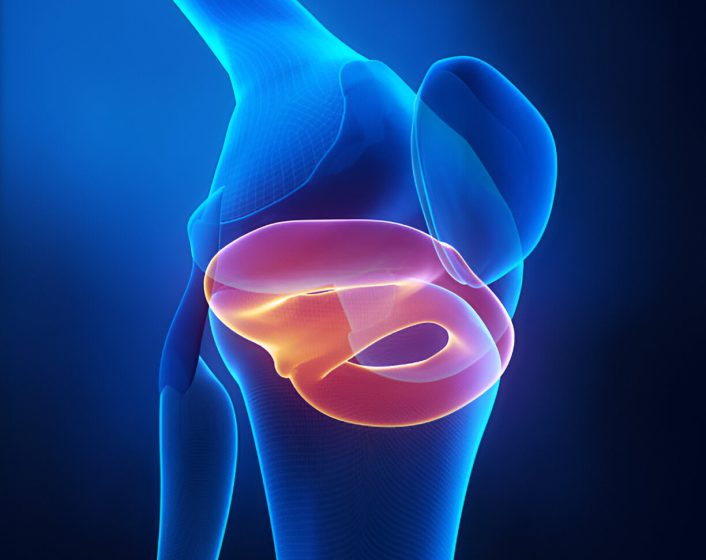

A meniscal injury involves damage to the cartilage in the knee, known as the meniscus, which acts as a cushion between the thigh and shin bones. This injury often occurs due to twisting or heavy lifting and is common in athletes. Symptoms include pain, swelling, stiffness, and difficulty moving the knee. Treatment options range from rest and physical therapy to surgical repair, depending on the severity of the tear. Early diagnosis and treatment are essential for effective recovery.

Meniscal Injury